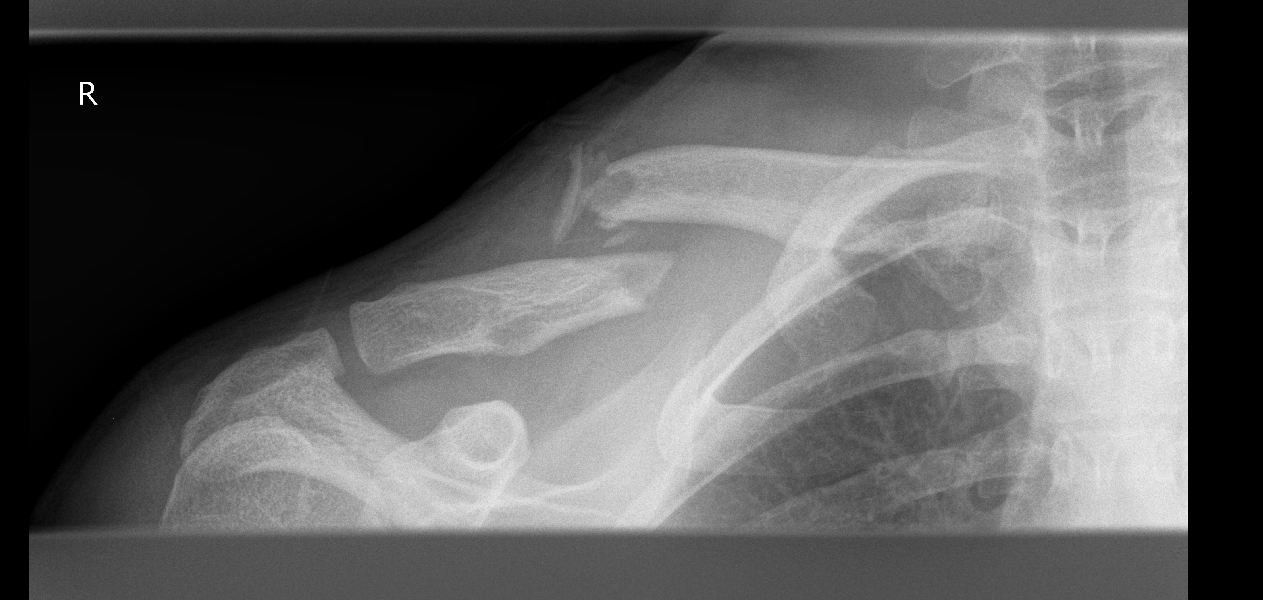

Habe mir am 26.05 das rechte Schlüsselbein gebrochen, allerdings nur einmal und nicht mehrfach.

Habe jetzt ne schöne Titanplatte auf dem rechten Schlüsselbein die mit insgesamt 6 Schrauben befestigt ist.

Im Anhang habe ich mal 2 Röntgenbilder hochgeladen, habe die von dem Krankennhaus auf CD bekommen.

Weil die beiden Bruchenden sich dann halt schon übereinander gelegt hatten (sieht man gut auf dem ersten Bild) musste halt eine Platte drauf die das ganze in die richtige Stellung bringt.

Nachteil dabei ist aber dass man hinterher wenn nach ca 1 Jahr die Platte + Schrauben wieder raus kommen man immernoch die Schraubenlöcher im Knochen hat und somit ne neue Schwachstelle da hat.